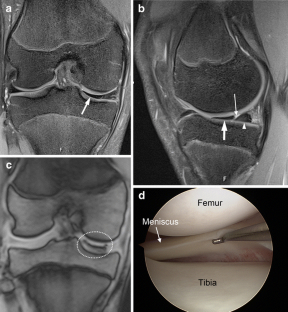

A total of 914 consecutive exams from 875 patients (524 men; mean age, 35 years) were reviewed. Vacuum phenomenon was found in 12 patients (prevalence 1.3%). In six (50%) patients, VP mimicked a meniscal tear, with four cases simulating a torn medial discoid meniscus. The VP signal was not easily differentiated from meniscal signal on most sequences in most cases (9/12). Gradient-recalled echo (GRE) localizer images proved most definitive, with 3D SPACE images the next most effective. Fast spin echo (FSE) images were only occasionally able to differentiate VP from meniscus.

Rarely recognized on MR, VP can mimic meniscal pathology, potentially leading to inappropriate surgery. Because differentiation of VP from the meniscus is challenging on FSE at 3 T, radiologists should become familiar with the appearance of VP and review GRE localizer or 3D images carefully to avoid misinterpretation.